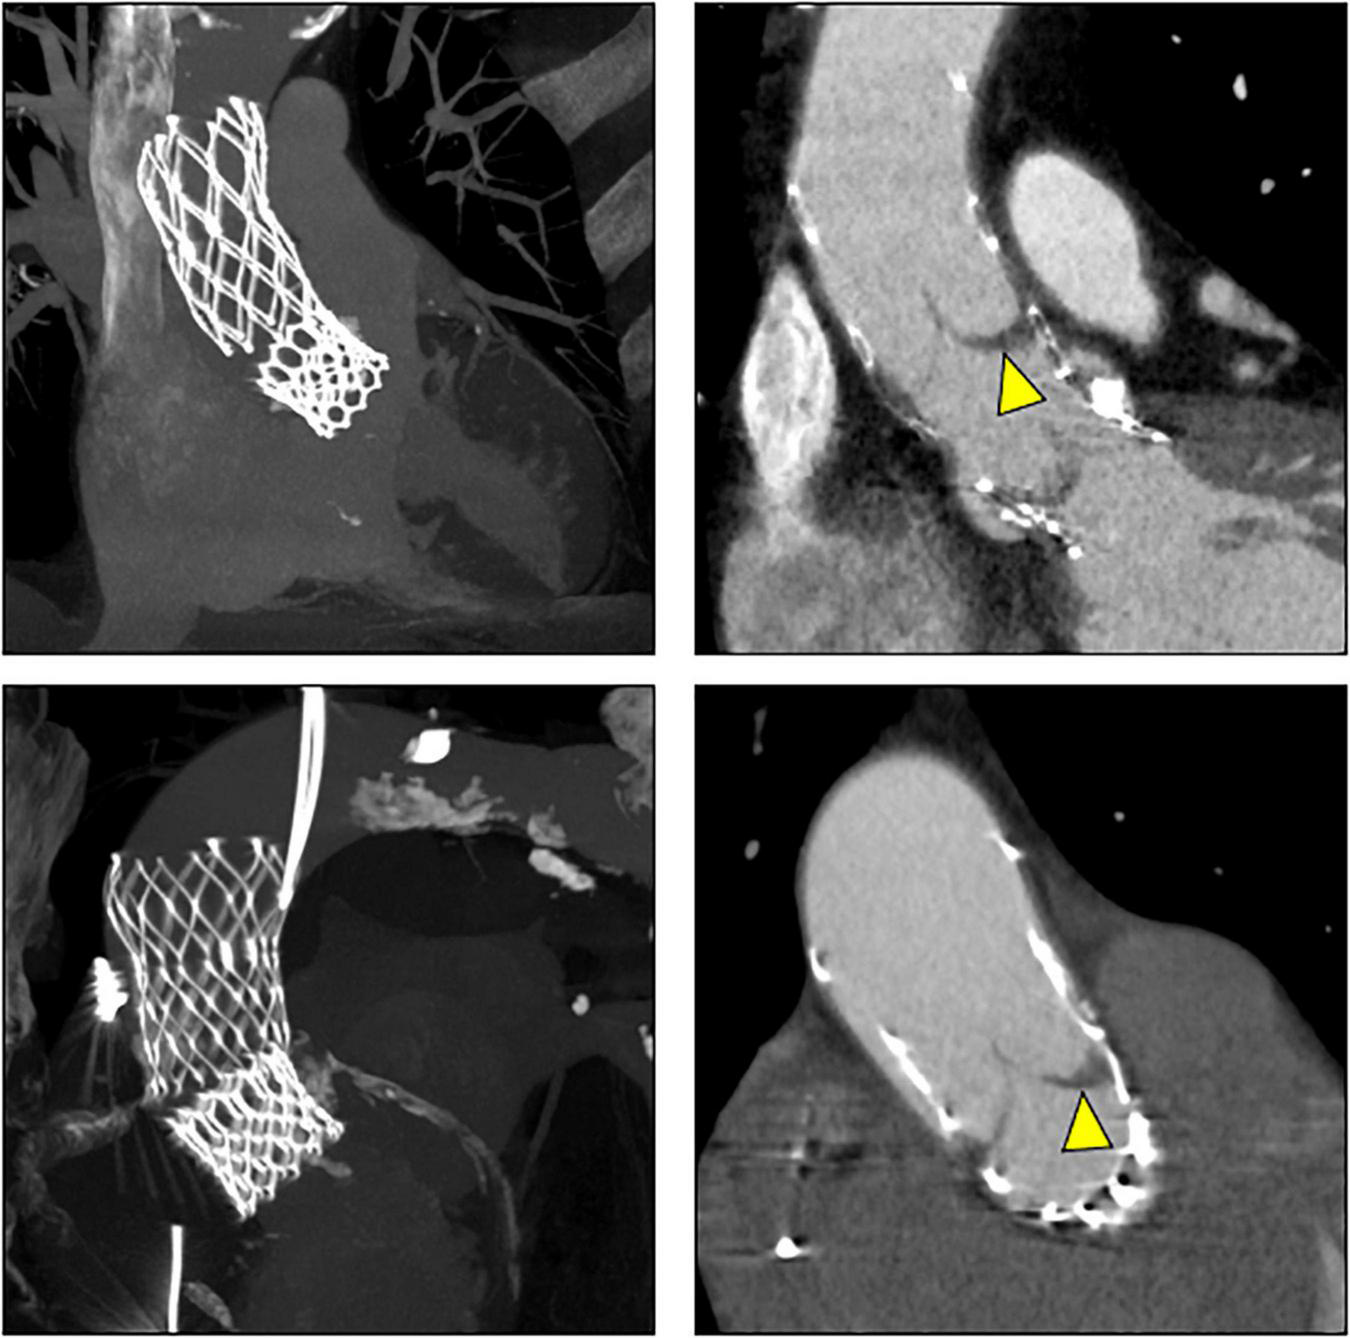

CT exams were performed on average 26.3 months after TAVI (range 2–84 months). Similar to the overall distribution in all TVEM patients (Figure 1B), the embolized valve was left in the aortic root or the ascending aorta in eight of the examined patients. Hypoattenuated leaflet thickening (HALT) was detected in two embolized valves (Figure 2). In these two patients stent frames showed no deformation. In addition, parts of the stent frame protruding into the aortic wall, yet without signs of dissection, were observed in three patients (Figure 3).

FIGURE 2

Subclinical valve thrombosis in embolized valves. In patients 9 (top) and 10 (bottom; see Table 5 for details), follow-up CT detected hypoattenuated leaflet thickening (arrow heads) in self-expanding valves embolized into the ascending aorta.

Subclinical leaflet thrombosis characterized by hypoattenuated leaflet thickening (HALT) is a frequent finding in transcatheter bioprosthetic aortic valves with a prevalence of up to 28% in short- and long-term CT follow-up (4, 5, 14). To our knowledge, our study is the first to systematically examine embolized valves by CT after mid- to long-term follow-up. HALT was detected in the embolized valves in two TVEM patients (Figure 2). Since the number of patients in our imaging sub-study is low it is not possible to draw definite conclusions. Of note, both patients with HALT did not take oral anticoagulants which have been shown to prevent the formation of leaflet thrombosis. In addition, our findings advise some caution as parts of the upper crown of embolized self-expanding valves protruding into the aortic wall were observed in three patients (Figure 3). This is reminiscent of another case from our TVEM cohort complicated by valve embolization due to pop-up of a 25 mm Portico self-expanding valve. The embolized valve was snared and pulled into the ascending aorta to avoid coronary obstruction. After successful implantation of a second transcatheter valve (23 mm Edwards Sapien 3) the patient developed hemorrhagic shock. Angiography revealed perforation of the ascending aorta by a part of the upper crown of the THV protruding through the aortic wall. The valve was surgically removed, and the ascending aorta repaired on cardiopulmonary bypass (Figure 6). Accordingly, interventionalists should be aware of this potential complication when embolized valves have to be actively pulled up into the ascending aorta using a snare. Patients should be examined by CT in a timely fashion to rule out perforation of the ascending aorta if they develop hemodynamic instability in the postinterventional course.